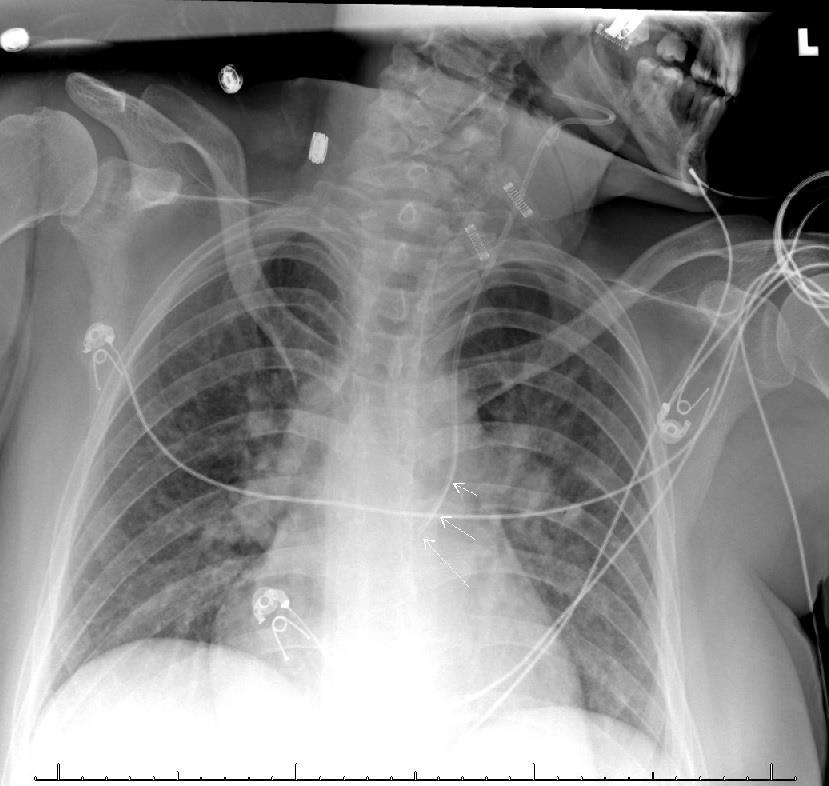

Anterior-posterior chest radiograph (CXR) obtained after placement of the central venous catheter revealed the catheter taking an atypical course, projecting over the left mediastinum, not crossing the midline (Image 1). A computed tomography of the chest demonstrated the catheter coursing from the left internal jugular into the left internal mammary vein (Images 2 and 3). The patient was ultimately admitted to the intensive care unit, and the central venous line was removed at the bedside and replaced.

Chest radiography will demonstrate a catheter coursing over the left side of the chest, which can also be seen in other misplaced central venous lines (pleural space, arterial, etc) While misplacement into arterial, soft tissue, or other non-venous sites is usually quickly identified via the above confirmatory measures, misplacement into unusual, undesired venous sites, which could also include the pericardiophrenic vein or the subclavian vein, may only be recognized with subtle abnormal imaging findings. A misplaced catheter in this position should not be used due to the risk of vessel damage and should be removed. Emergency physicians should be aware of the rarer possible complications of this commonly performed procedure and their appearance on imaging studies.